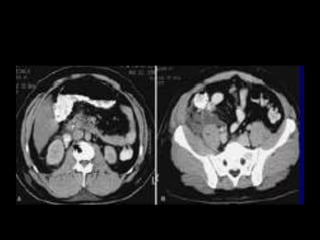

Diagnostico

• USG S-80%, E-85%

• UROGRAFIA ENDOVENOSA S-82 Y E-85

Arteriografía S-89 Y E-91

TAC S-95 Y E-97

•

GRADO ll

GRADO lll

GRADO IV

• 90% Tratamiento conservador